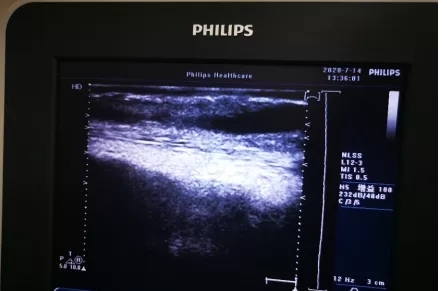

自体内瘘附壁血栓▲